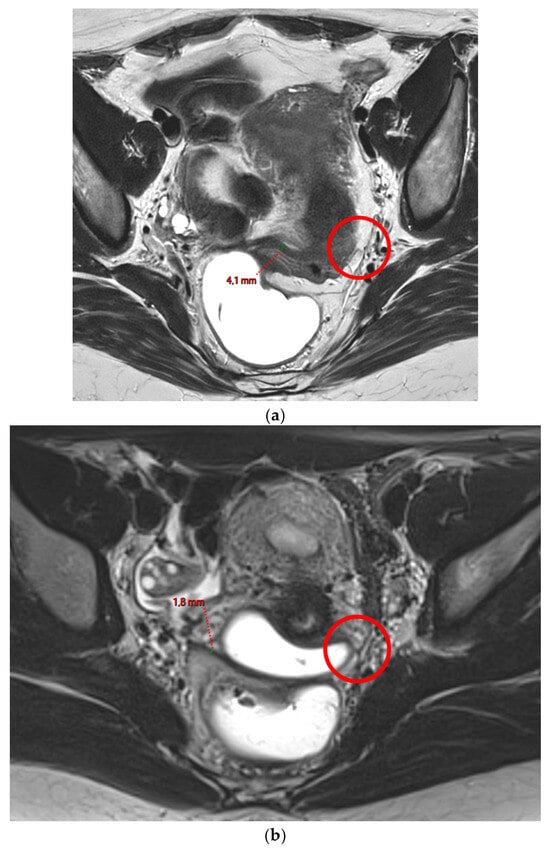

A type 1 USL (Figure 1) is not visible on MRI scans.

Figure 1. Pelvic MRI scans of two patients with non-visible left USLs (HTD type 1). (a) Axial T2WI shows a visible and measurable right USL but a non-visible left USL (red circle). (b) Axial T2WI shows a visible and measurable right USL but a non-visible left USL (red circle).